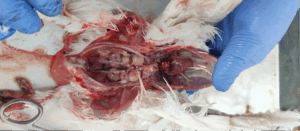

- All the visceral organs are exposed by this cutting.

- Internal organs should be checked properly in situ before removing one by one.

- Samples for microbiological analysis are collected maintaining aseptic procedures at this stage.

- The lungs, liver, heart should be removed carefully by gentle traction and with the help of a sharp scalpel or scissor cutting through wherever necessary.

- The GIT is removed in the same way.

- Kidneys, ovaries, oviducts should be observed and removed carefully.